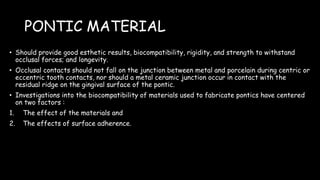

The document discusses pontic design for fixed dental prostheses. It covers pretreatment assessment of residual ridge contours, classifications of ridge deformities, surgical modification techniques, and ideal requirements for pontics. Pontic designs are classified based on their shape and materials. Factors in pontic selection include esthetics and oral hygiene. Common designs for anterior and posterior regions are described, including sanitary, ovate, and saddle pontics. Biological considerations for pontic design involve maintaining the residual ridge, abutment teeth, and supporting tissues.